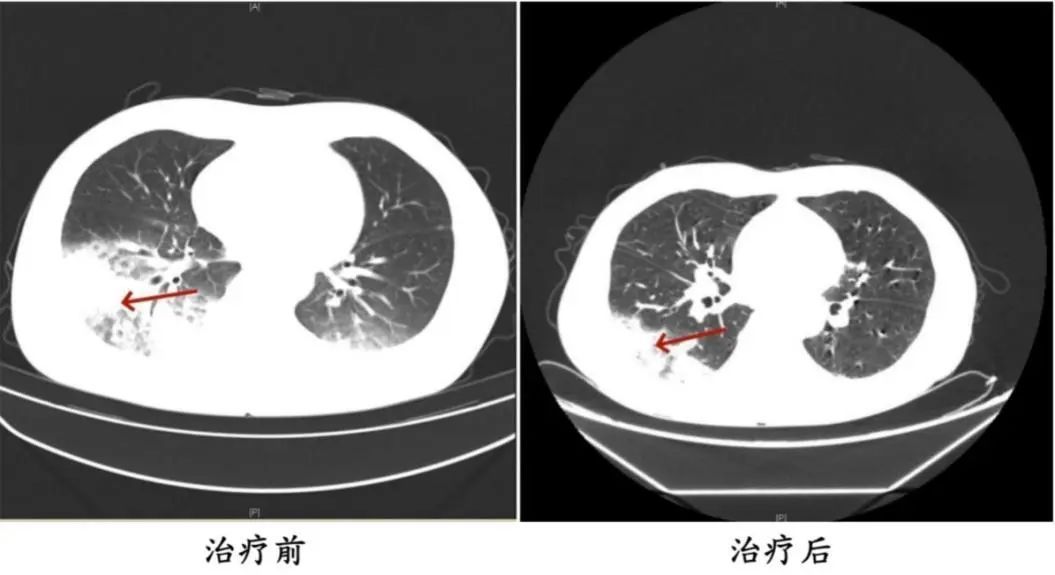

周先生治療前后的肺部CT影像

醫生判斷患者有可能感染了軍團菌,建議患者完善纖支鏡檢查,留取肺泡灌洗液標本查找病原體。最終,患者肺泡灌洗液NGS(Next-Generation Sequencing,下一代測序)檢測結果顯示:嗜肺軍團菌,明確診斷為軍團菌肺炎。醫生馬上調整治療方案,改用可覆蓋嗜肺軍團菌的一線用藥抗感染,患者體溫逐漸下降,次日體溫恢復正常,經過后續治療康復出院。